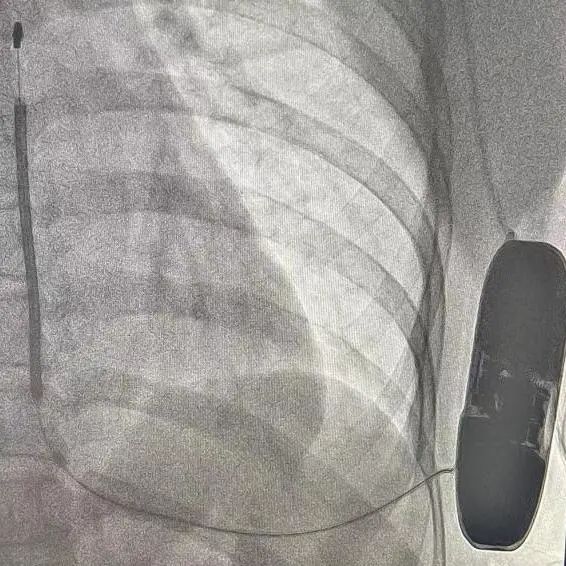

手术在全麻醉下进行。常规消毒、铺巾,取左腋中线平等第5-6肋为预定点,切开一约7cm切口,逐层将皮下组织分离直至肌层,在前锯肌与背阔肌之间寻找到深筋膜层,以确保囊袋在患者的脂肪层下并且足够容纳装置。

再次于胸骨柄右缘1cm为预定点,切开一长约4cm切口,逐层分离至深筋膜层,预埋两根缝合线用导引针,于切口间建立隧道,利用隧道针将电极沿皮下置入囊袋。再以切口位置建立隧道,同样以隧道针将导线头端沿深筋膜层,送至胸骨柄上缘(距切口14cm处,于切口处固定电极导线,囊袋处连接脉冲发生器(S-ICD A209),固定脉冲发生器于深筋膜层。

排除空气后关闭深筋膜层,进行DFT测试。两位患者均采用50HZ,200MA交流电方式进行诱颤,SICD均正确识别且65J除颤一次成功,除颤阻抗分别为85欧姆和59欧姆。缝合皮肤,术区纱布覆盖,包扎,弹力绷带加压包扎止血。手术圆满成功。第一台手术耗时2小时,第二台手术仅耗时1个半小时。

患者一:

患者二:

根据Praetorian评分,在术后影响下评估。两位患者评分均为30分。

(Praetorian评分越低,术后除颤风险越低,30分为最低分数)